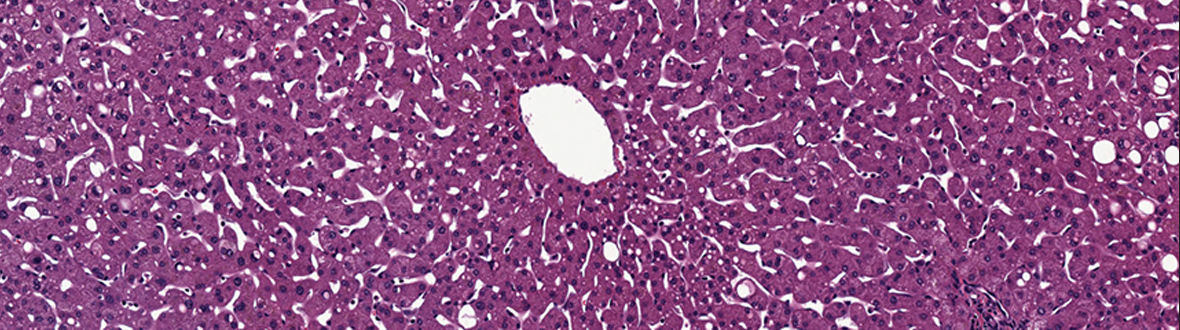

LifeNet Health’s LifeSciences Division created a human tissue and cell-based in vitro biology platform by leveraging its innovative technology-driven transplantation and preclinical research programs.  The LifeSciences Division developed a vertically integrated supply chain for human tissue recovery and cell preparation, which supports the increasing demands for human biospecimens, primary cells and hepatocytes for scientific research, drug discovery and safety testing. The application of three dimensional matrices and human cellular models will enable significant scientific improvements for more relevant biologic experiments.

LifeSciences products and services include: human biospecimens, hepatocytes and other primary cells, cell culture media including human ECMs (HuGentra), oncology 3D HuBiogel™- based biology testing services, and custom requests.